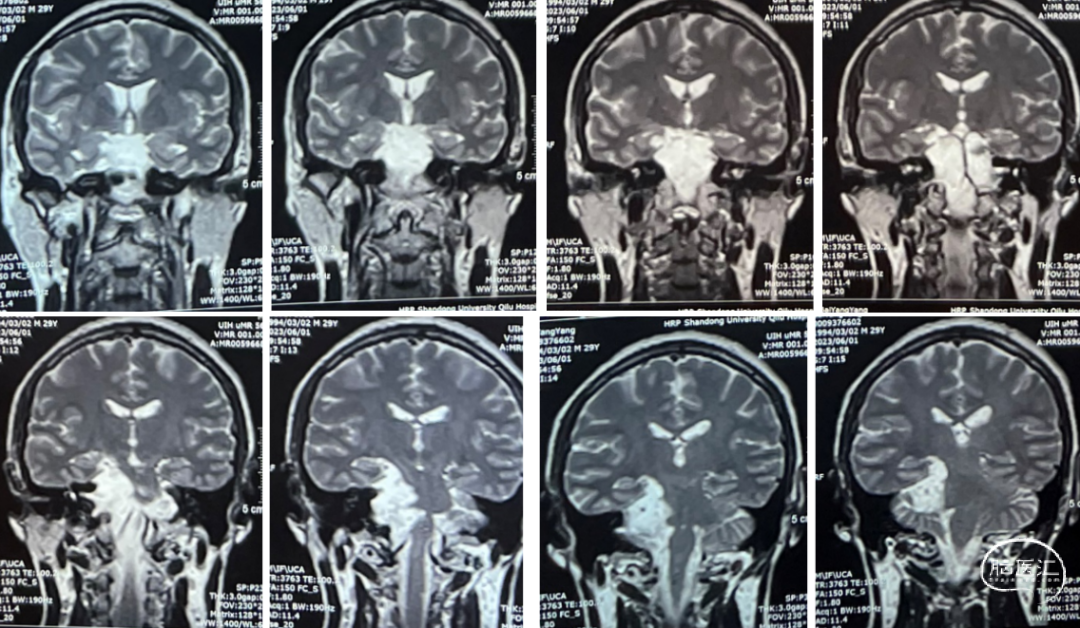

患者情况

查体:右侧听力下降。